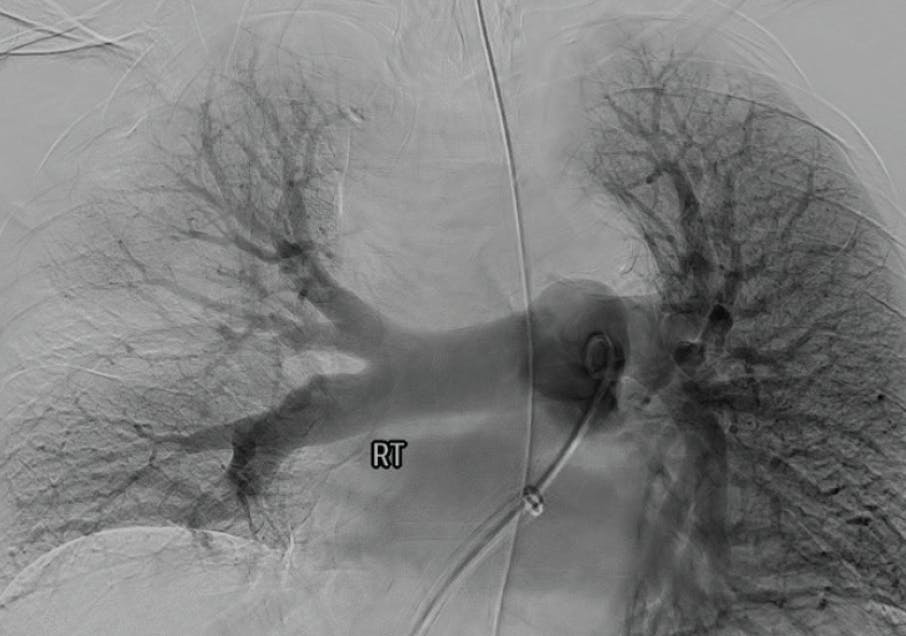

Figure 1. Right and left initial angiograms.

INTERVENTION

Access was achieved in the right common femoral vein (CFV), and initial diagnostics revealed an elevated mean PA pressure of 34 mm Hg. After selection of the right lower lobar PA, the venotomy site was dilated over a wire and a 16-F, 33-cm Gore DrySeal sheath was placed. Under fluoroscopic guidance, a 16-F, 100-cm Lightning Flash XTORQ was advanced into the right PA and two passes were performed. Subsequently, the device was tracked into the left PA and two additional passes were performed. Figure 2 shows the amount of clot extracted. Reassessment of hemodynamics revealed improvement in mean PA pressure from 34 to 17 mm Hg, reflecting an on-table drop of 17 mm Hg. Additionally, selective bilateral pulmonary angiography showed significant improvement in perfusion (Figure 3). By the conclusion of the case, the patient was weaned from FiO2 of 15 L/min to room air.

Figure 3. Post-thrombectomy right and left angiograms.